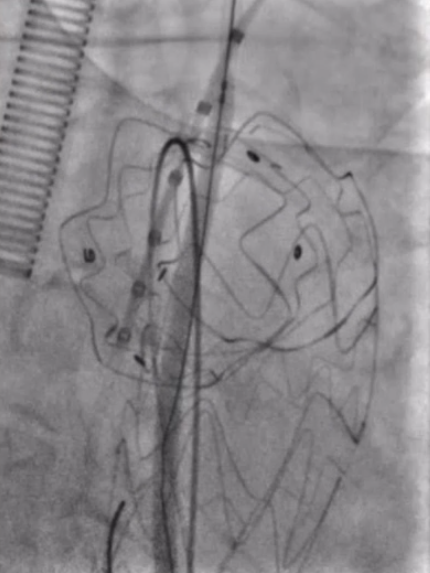

先后导入4mm、6mm和8mm球囊对覆膜区进行扩张。考虑到患者颈总动脉存在较严重的动脉硬化,为避免置入大血管鞘带来的风险,选择使用10-40mm自膨式裸支架重建左颈总动脉,使用10-60mm球囊进行后扩张。扩张后,支架形态满意,成功恢复了左侧颈总动脉血流。

图2

更换MUSTANG 8-40mm球囊进一步扩张开窗处(图2)